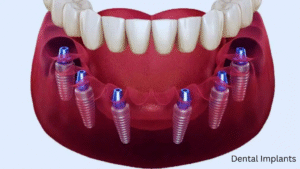

When it comes to oral rehabilitation, full-mouth dental implants have emerged as one of the most reliable and life-changing treatment options

When patients face multiple missing or damaged teeth, the most effective and long-lasting solution is full mouth dental implants. Unlike